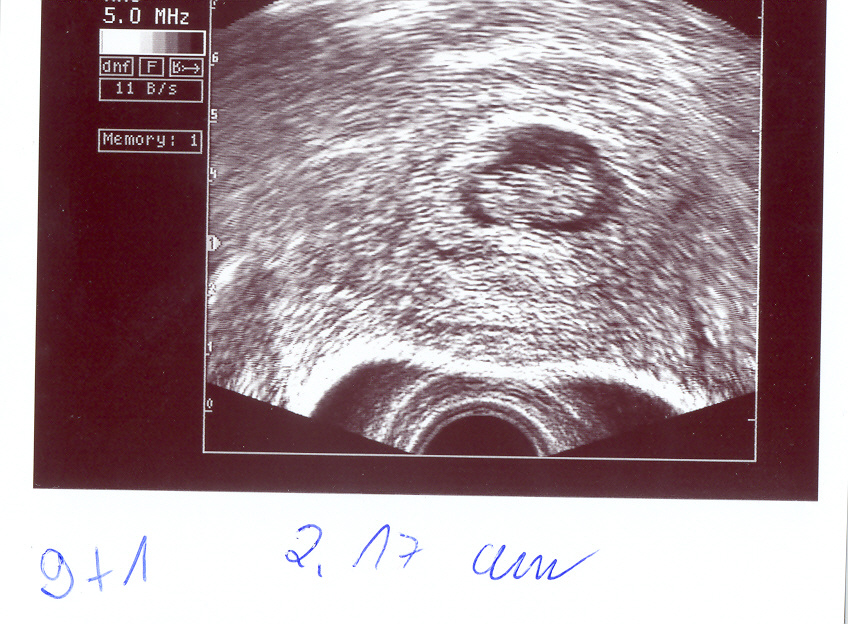

So, ich werde jetzt mal meine US-Bildchen scannen und dann ins Album stellen